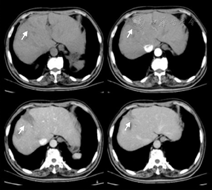

(1)病例特点:患者男性,69岁,以"消瘦厌食伴上腹胀3个月"于2013年1月9日收入我科,查体:未见明显阳性体征。既往史:无相关病史。实验室检查:肿瘤标志物AFP、CEA、CA19-9及其他生化检查未见明显异常。胃镜:十二指肠球部降交界移行处见隆起性病变,呈菜花样,表面充血、糜烂。超声胃镜提示:十二指肠隆起性病变(图7),活检病理回报:十二指肠黏膜慢性炎症。增强CT考虑恶性(图8)。(2)治疗:手术行胰十二指肠切除术。大体标本呈黄白色、鱼肉状、质硬肿物,边界模糊。(3)术后病理诊断为胰头炎症性肌纤维母细胞性肿瘤。(4)预后:术后电话随访4年余未见明显复发,恢复良好。